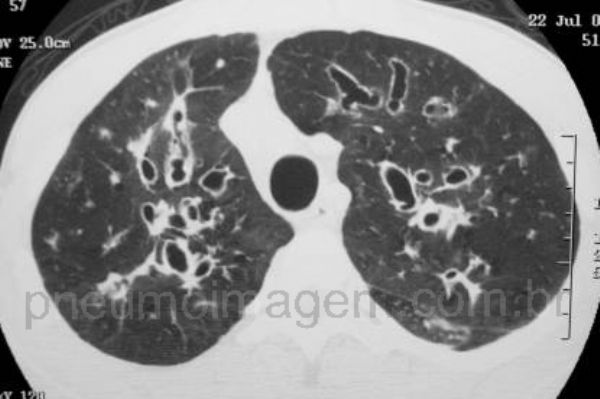

Antigamente era considerada uma doença exclusivamente da infância, uma vez que os pacientes dificilmente atingiam a vida adulta. Com os novos tratamentos, a expectativa de vida de um paciente que nasce com FC está ultrapassando os 40 anos. Formas mais leves da doença existem e a doença pode se manifestar algumas vezes de forma tardia. O caso em questão é de um rapaz cujo diagnóstico da FC ocorreu somente após os 20 anos de idade. Neste corte tomográfico observam-se as bronquiectasias centrais predominando nos lobos superiores.

Previously, CF was considered an exclusively childhood disease, since patients hardly reached adulthood. With the new treatments, the life expectancy of a patient born with CF is over 40 years old. Lighter forms of the disease exist and the disease may sometimes manifest late. The case in question is of a man whose diagnosis of the CF occurred only after the 20 years of age. In this CT slice we can observe the central bronchiectasis predominating in the upper lobes.